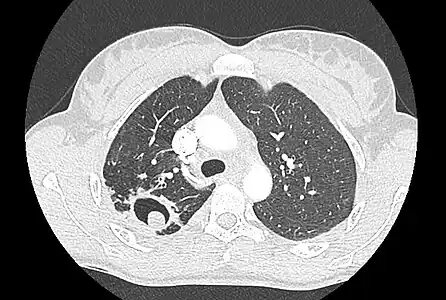

Sur la radiographie pulmonaire, un aspergillome simple apparaît comme un nodule dense, le plus souvent entouré d'un croissant aérique[11]. La radiographie seule ne suffit pas au diagnostic ; un scanner est recommandé[29]. Sur le scanner thoracique, le centre de la cavité est occupé par l'aspergillome[58]. La pseudo-tumeur bouge dans la cavité lorsque le patient change de position (signe de Monod)[58]. Dans l'aspergillome simple, il n'y a pas d'évolution entre les examens et la paroi de la cavité est le plus souvent fine[13]. Un aspergillome complexe[13] présente en revanche l'aspect d'une cavité (ou plusieurs) à parois épaisses, comportant en son centre une truffe aspergillaire. Il existe parfois un début de fibrose pulmonaire[59]. La plèvre adjacente a également un aspect fibrosé, et l'évolution radiologique est lente, mais toujours vers l'aggravation[13]. Un halo en verre dépoli peut également entourer les lésions[45].

- Aspect scannographique typique d'un aspergillome développé dans une caverne tuberculeuse.

- Le changement de position modifie la position du grelot aspergillaire dans la cavité (signe de Monod).